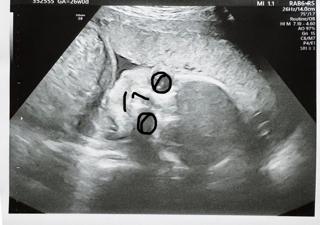

写真:26w0d:ちゃまたろーさん:一卵性双子ちゃん

4Dでは胎盤に隠れちゃって顔見れず、2Dで先生が撮ってくれました

次28wの時がラストチャンスになるので次回が楽しみ

720gと男の子割には小さめなのかな?

毎日元気に動いてくれるのでこのまま順調に成長してほしいです